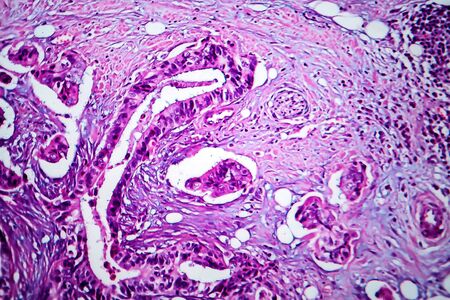

Breast cancer of the woman diseased tissue 100x